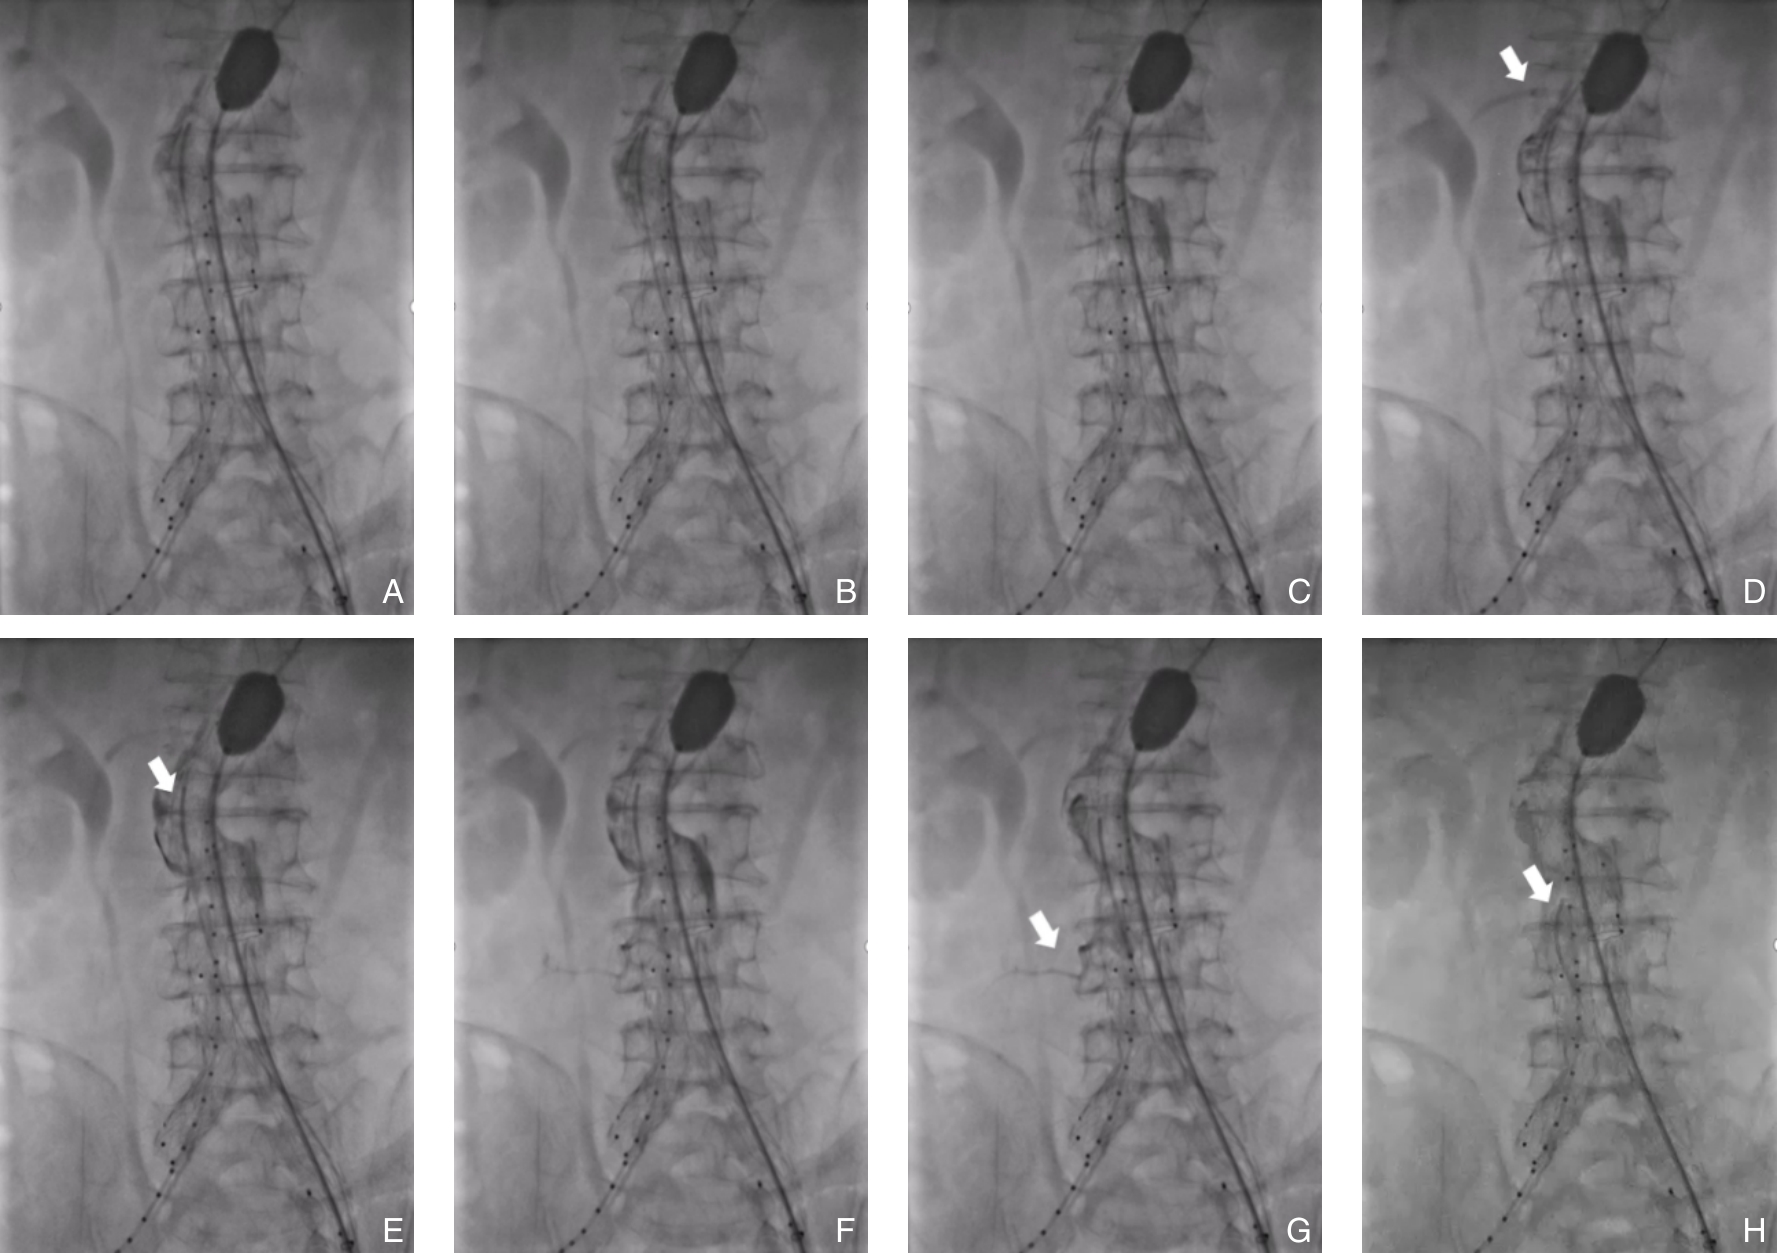

2026, 35(1):141-148. DOI: 10.7659/j.issn.1005-6947.250622

Abstract (79) HTML (119) PDF 1.24 M (183) Comment (0) Favorites

Abstract:Background and Aims Hepatocellular carcinoma (HCC) presenting initially with bone metastasis is uncommon, and metastasis to the appendicular skeleton is particularly rare. These cases often lack typical liver disease history, elevated alpha-fetoprotein (AFP), or characteristic imaging findings, leading to frequent misdiagnosis or delayed diagnosis. This study reports a rare case of occult HCC presenting with humeral metastasis and reviews the literature to improve clinical recognition and management.Methods The clinical data of a 42-year-old male patient presenting with humeral metastasis as the initial manifestation admitted in August 2025 were retrospectively analyzed, including laboratory tests, multimodal imaging findings, histopathological and immunohistochemical results, treatment, and follow-up outcomes. Relevant literature was also reviewed.Results The patient presented with left shoulder pain. Imaging revealed osteolytic destruction of the left humerus. PET/CT incidentally detected multiple hepatic lesions without significant FDG uptake. Contrast-enhanced ultrasound demonstrated atypical enhancement patterns, initially suggesting a perivascular epithelioid cell tumor. Histopathological and immunohistochemical examination of biopsy specimens from both the humeral and hepatic lesions confirmed moderately differentiated hepatocellular carcinoma with humeral metastasis (CNLC stage IIIb). The patient received systemic therapy with sintilimab plus bevacizumab, followed by transcatheter arterial chemoembolization. After 6 months of follow-up, the intrahepatic lesions had decreased in size, the bone metastasis remained stable, and pain symptoms were significantly relieved.Conclusion HCC presenting with humeral metastasis as the initial manifestation is extremely rare and may lack typical imaging and serological features. Clinicians should consider HCC in patients with unexplained bone metastasis even in the absence of liver disease history or elevated AFP. Multimodal imaging and pathological biopsy are essential for accurate diagnosis and appropriate management.